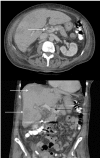

Pylephlebitis is a rare condition with a high mortality risk if not recognized and treated early. The most common symptoms include fever and abdominal pain, with the majority of cases manifesting with a polymicrobial bacteremia. We report an elderly woman with pylephlebitis presenting with fever, abdominal pain, diarrhea, and vomiting, likely secondary to a polypectomy 6 weeks prior. Abdominal CT revealed portal vein thrombus and blood cultures grew Streptococcus milleri and Haemophilus parainfluenza type V. Pylephlebitis should be considered when symptoms and signs of infection develop following endoscopic procedures, particularly in patients with an underlying hypercoaguable disease.